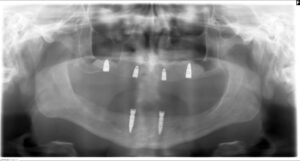

インプラントを下顎に2本、上顎に4本埋入し、

その上にインプラントオーバーデンチャー(インプラントで支える入れ歯)を装着しました。

術後約3〜4か月でインプラントと骨の結合を確認後、オーバーデンチャーを装着し、治療を終了しました。

術後

上顎(インプラント 4本) ¥1,305,000(税抜)

下顎(インプラント 2本) ¥856,000(税抜)